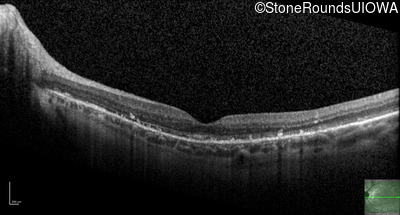

Optical Coherence Tomography - Right - 20/25 +1

Exemplar / OCT Stack